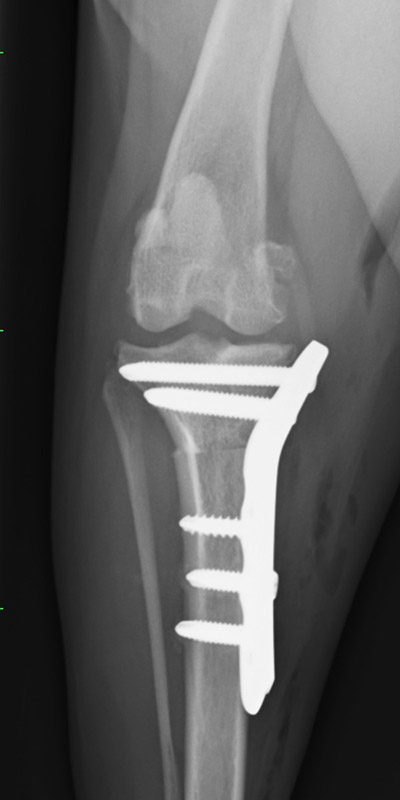

脛骨骨折

ウェルシュコーギー(4歳)

散歩中に転倒

手術前

手術後